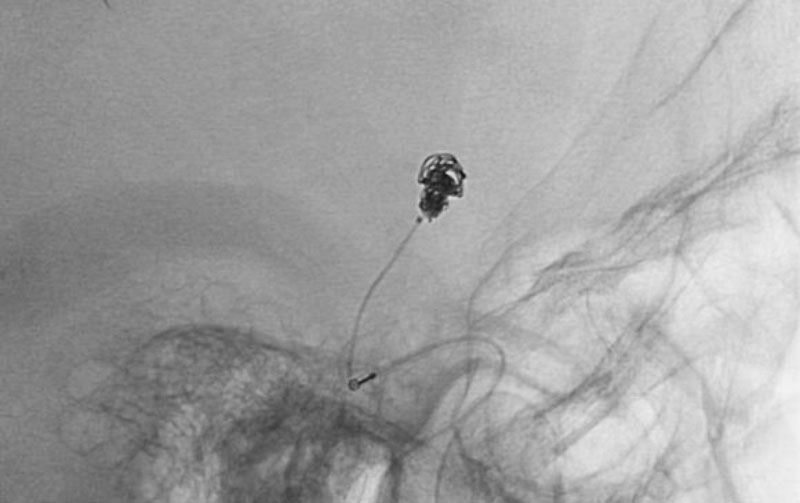

'25年11月

くも膜下出血

破裂性内頚動脈解離

40代

救急外来

No.1594 手術前

No.1594 手術中

No.1594 手術後